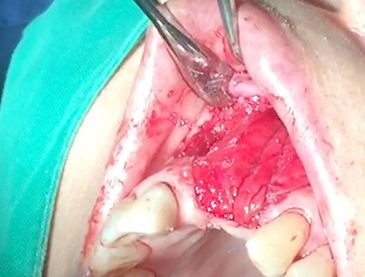

Implants/Bone Grafting

Partial edentulous clinical cases